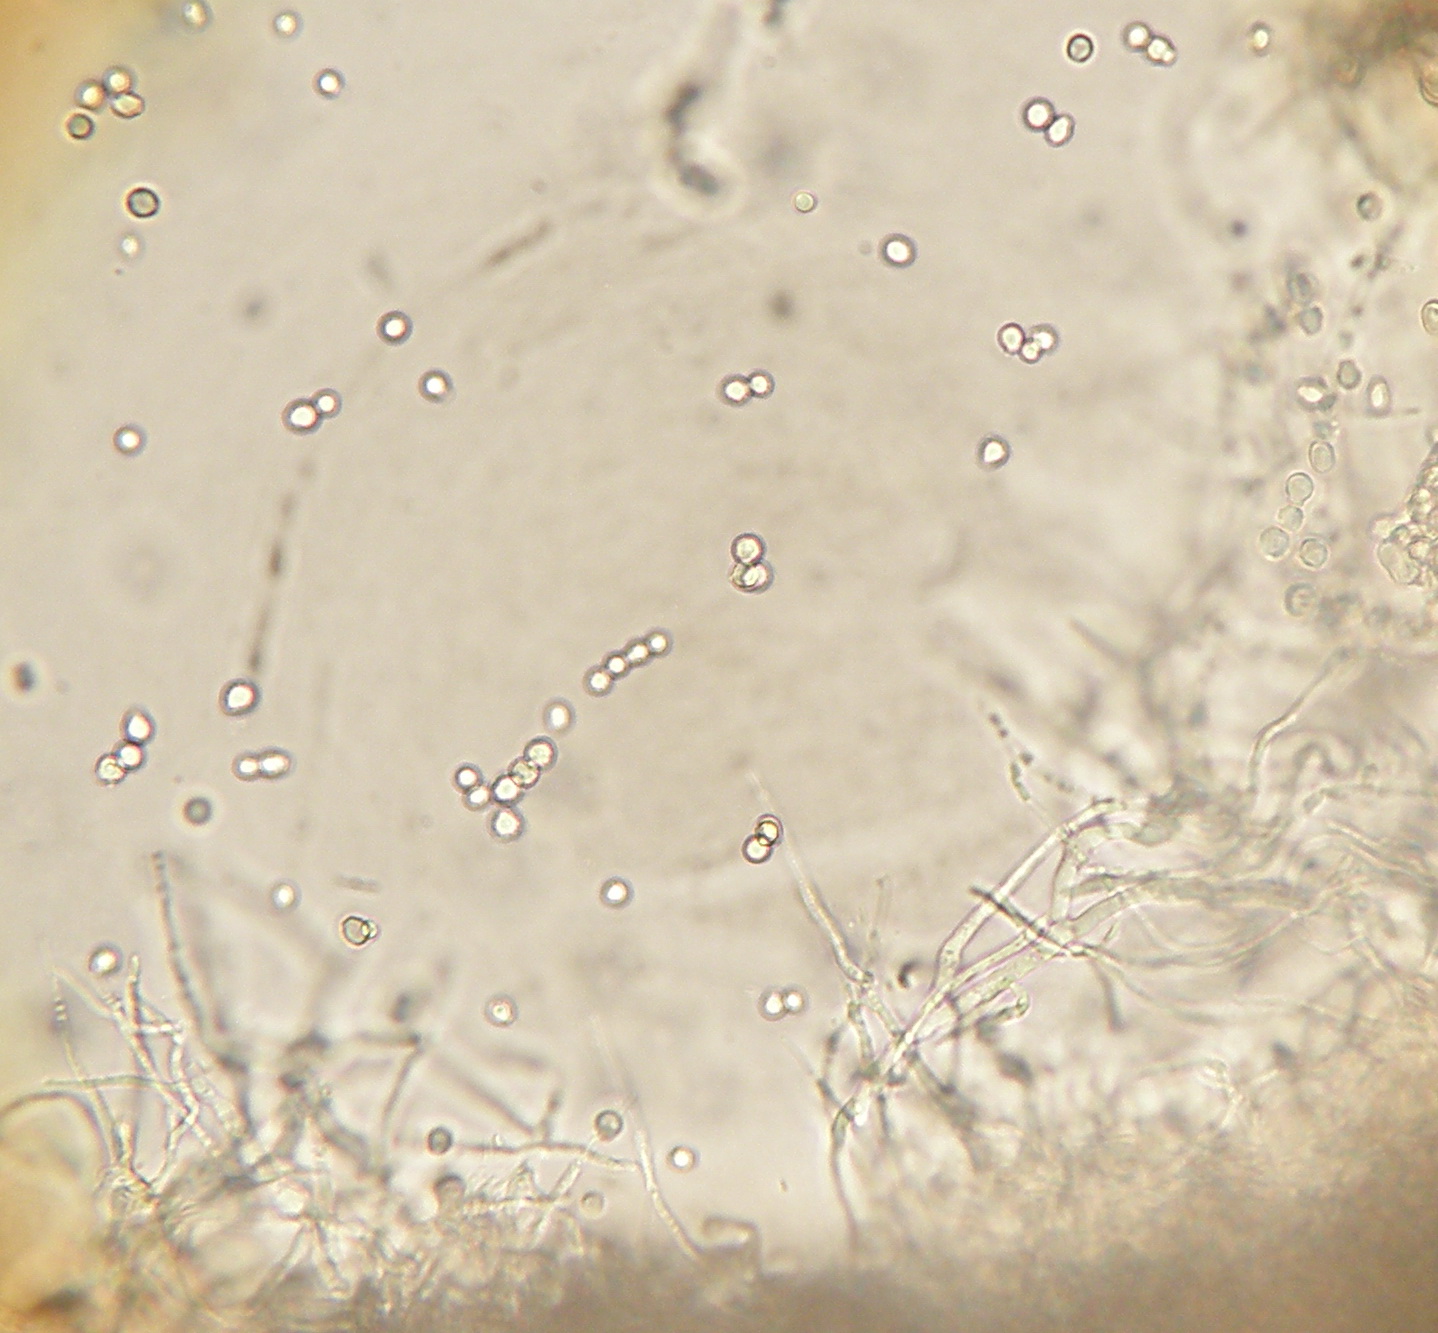

| Células conidiogenas simples ou agrupadas em pincel. Conideos de parede rugosa frequentemente em cadeia. |